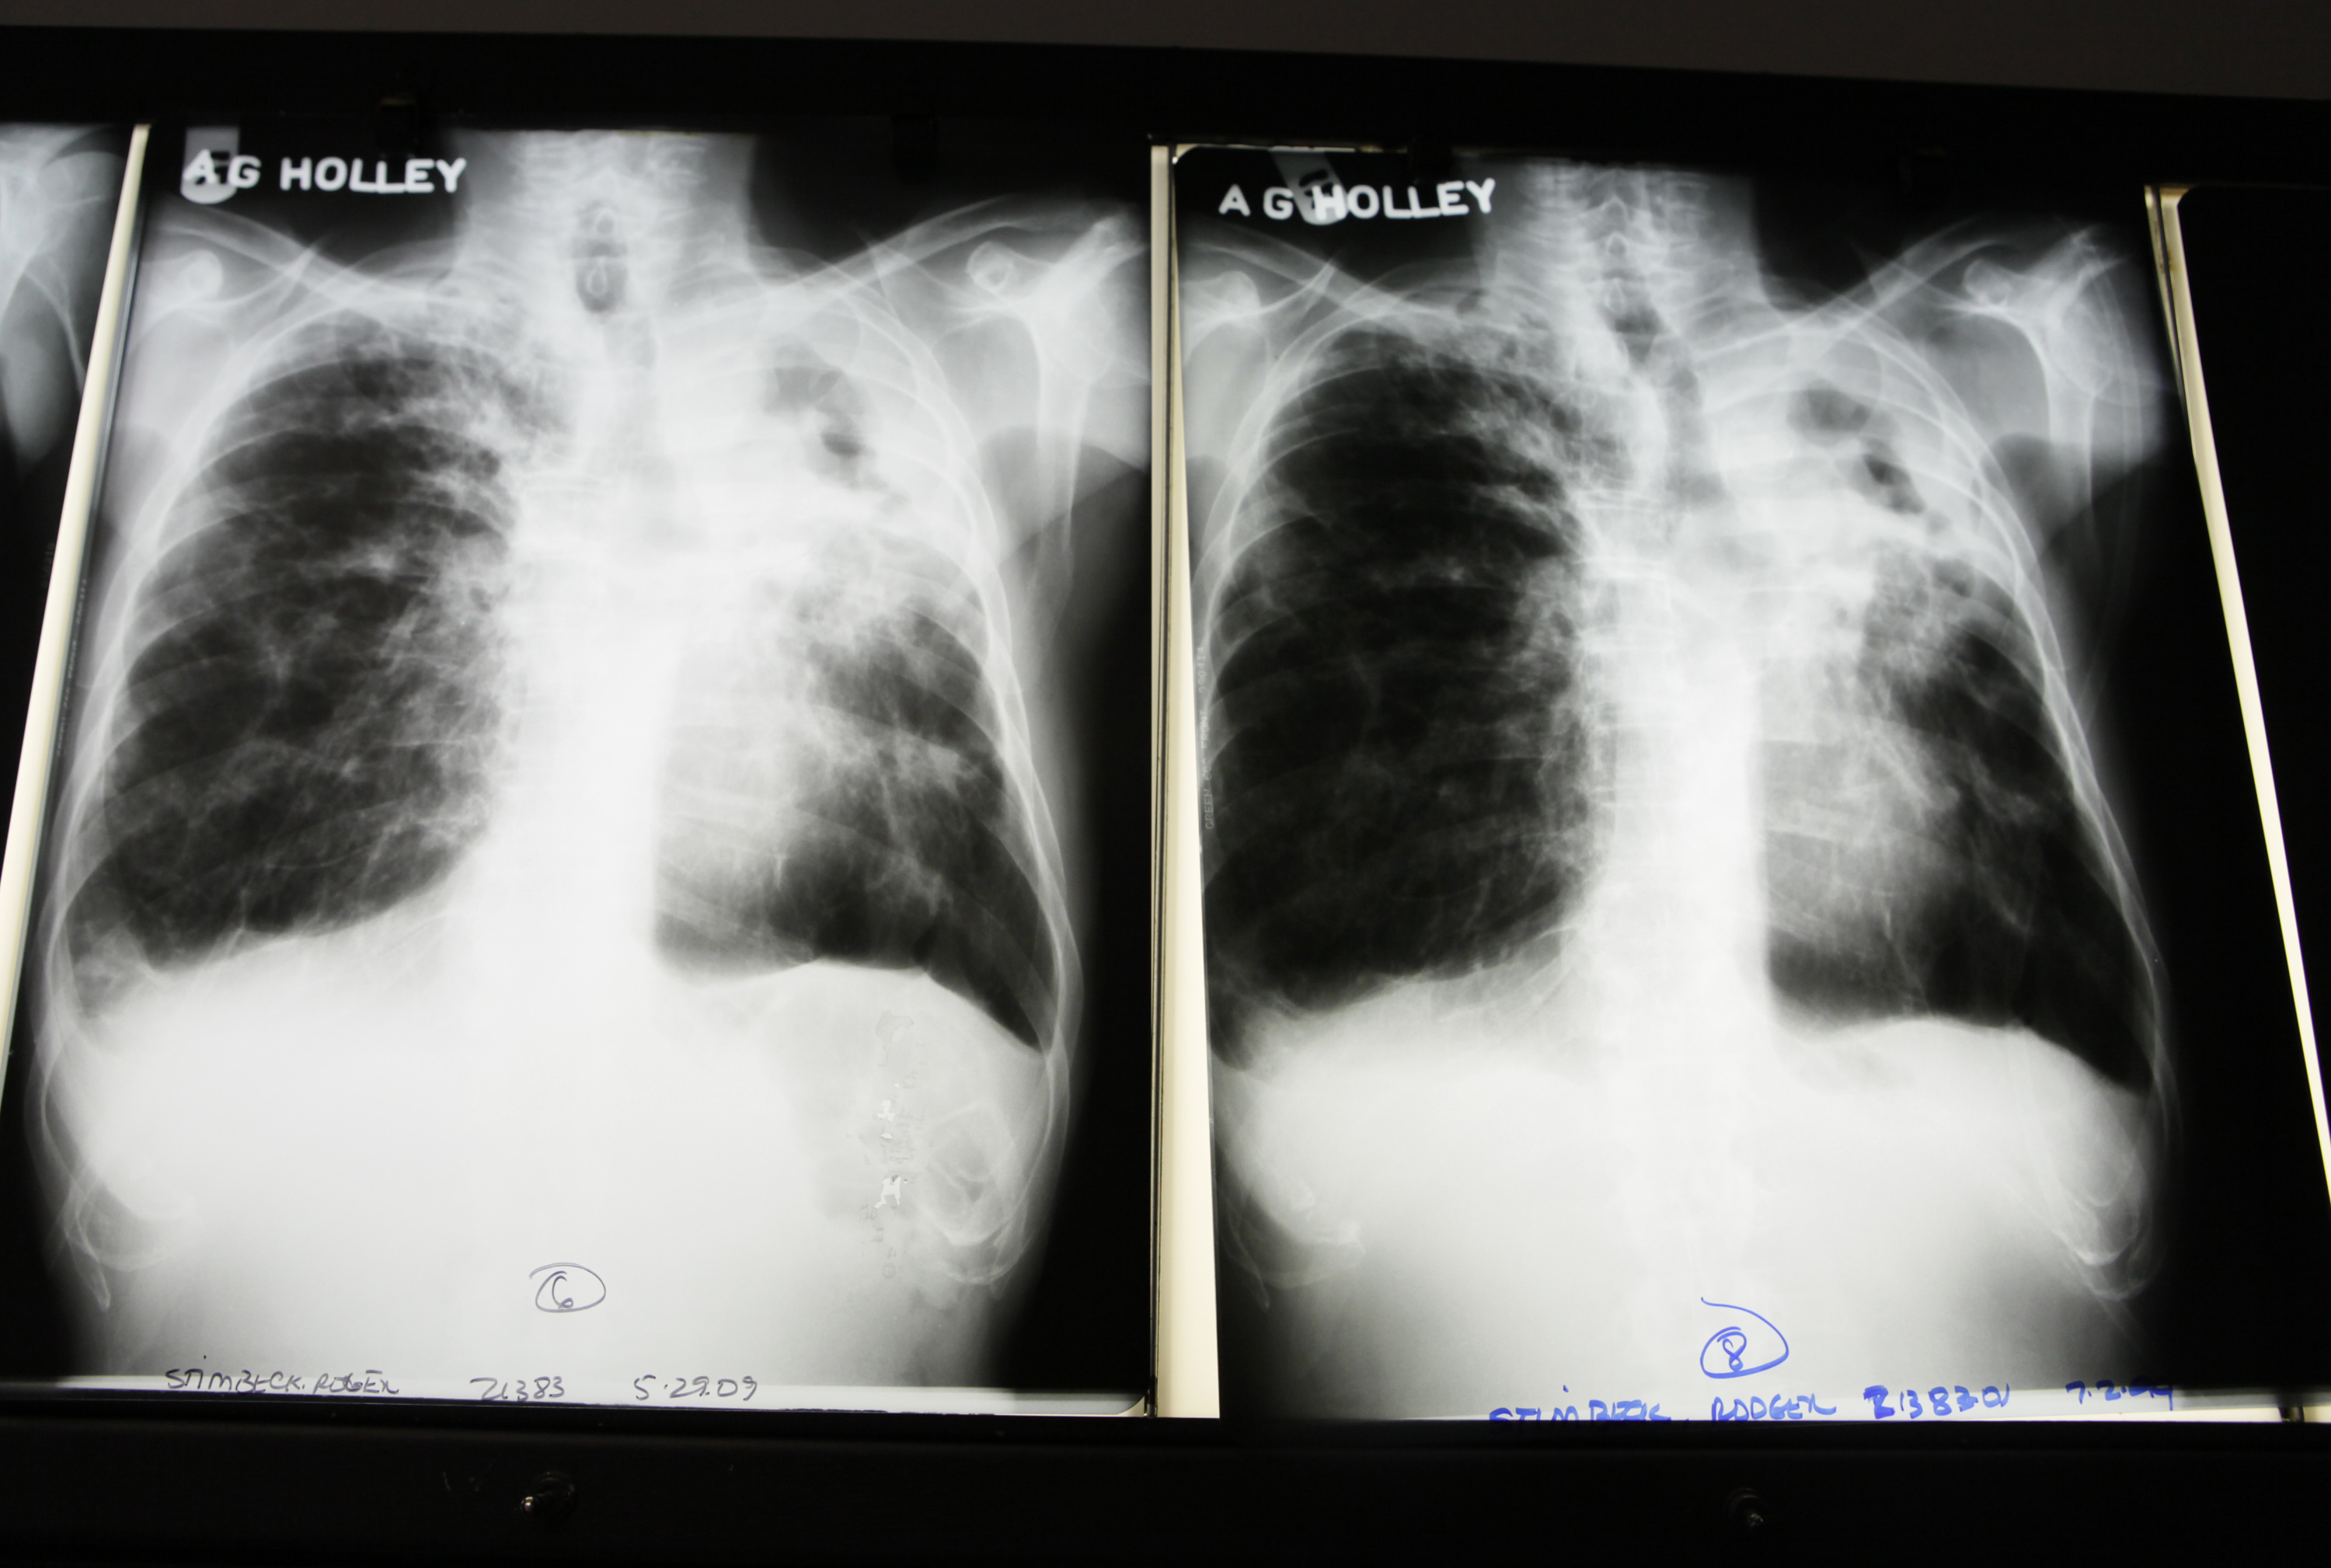

Last year, from March 1 to April 21, the National Reference Laboratory captured 39 positive samples. This year, the number was 57 for the same period. For the whole of 2020, from which the latest complete data comes there were 368 tuberculosis cases, with 464 a year earlier.